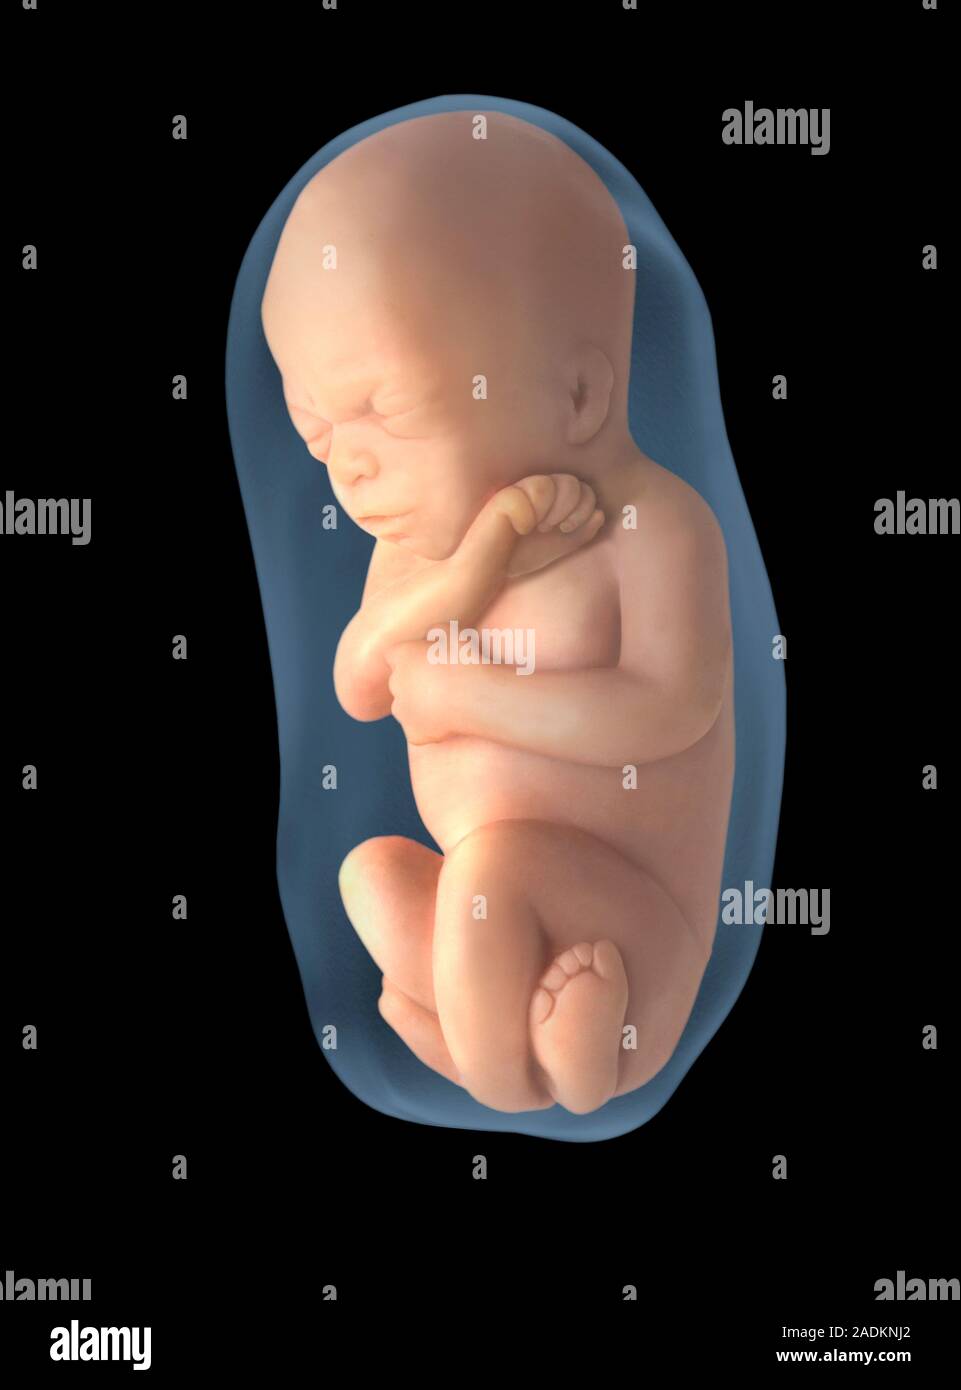

El feto. Ilustración de un feto humano tras 6 meses de desarrollo. Es visto en el saco amniótico

Saco Amniótico y Líquido. Adherida a la placenta se encuentra el saco amniótico, una membrana cerrada que rodea y protege al feto. Contiene líquido amniótico, que consiste en agua y sustancias disueltas. El líquido permite que el feto se mueva libremente hasta que crezca para llenar la mayor parte del espacio disponible.. Saco amniótico. Es un saco con paredes finas que rodea al feto durante el embarazo. El saco contiene líquido amniótico (líquido producido por el feto) y el amnios (membrana que cubre el lado fetal de la placenta), que proteje al feto de lesiones y ayuda a regular su temperatura. Ano. Es la apertura que se encuentra al final del canal anal.